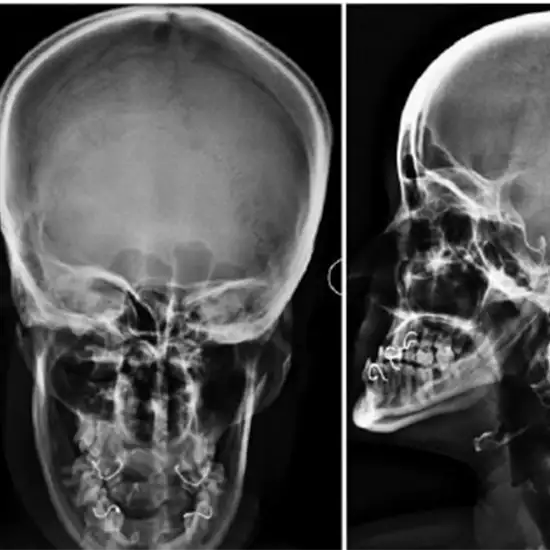

What is an X-ray Left Orbit PA & Lateral Views Test?

X-rays of the orbits are utilized to visualize the eye sockets (ring of thin bones containing the eye), the nasal bridge, and the cheekbones.